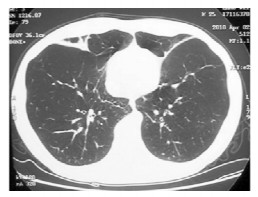

结果  1例26岁男性患者2年余前腹部、双胁、双腹股沟区多处出现皮炎, 皮疹处皮肤逐渐松弛; 1年余前开始出现活动后气短症状, 进行性加重。肺功能检查提示极严重阻塞性通气功能障碍, 胸部高分辨CT检查提示双侧全小叶型肺气肿。皮肤活检证实为皮肤松弛症, 胸腔镜下肺活检见肺气肿及多个肺大泡形成。肺组织电镜提示肺泡间隔增宽, 间隔内未见成结构的弹性纤维, 可见大量胶原纤维增生。予以持续小流量吸氧, 并予沙美特罗替卡松、噻托溴铵吸入治疗, 病情维持稳定, 复查肺功能略有好转。